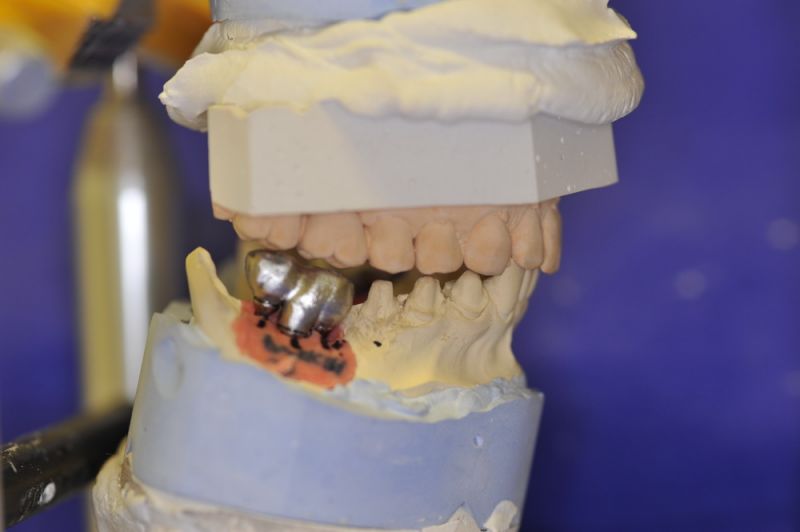

Es war eine Kombination aus Schmerzen bis an die Suizidgrenze, beschränkten wirtschaftlichen Möglichkeiten, sehr stark eingeschränkten Möglichkeiten der für Implantate zur Verfügung stehenden Knochenverhältnisse in einem stark atrophierten Unterkieferseitenzahnbereich und zudem dann auch noch durch auftretenden Problemen bei der Implantatinsertion und nachfolgenden Versorgung der Implantate.

Die Problematik der Implantatversorgungen kann man in einer Analogie folgendermaßen darstellen. Die räumlich beengten Zustände gleichen dem Tanz eines Paares auf einer Briefmarke, und der gleichzeitigen Schritt- und Fusshaltung, dass beim Tanzen die Schuhe geputzt werden können!